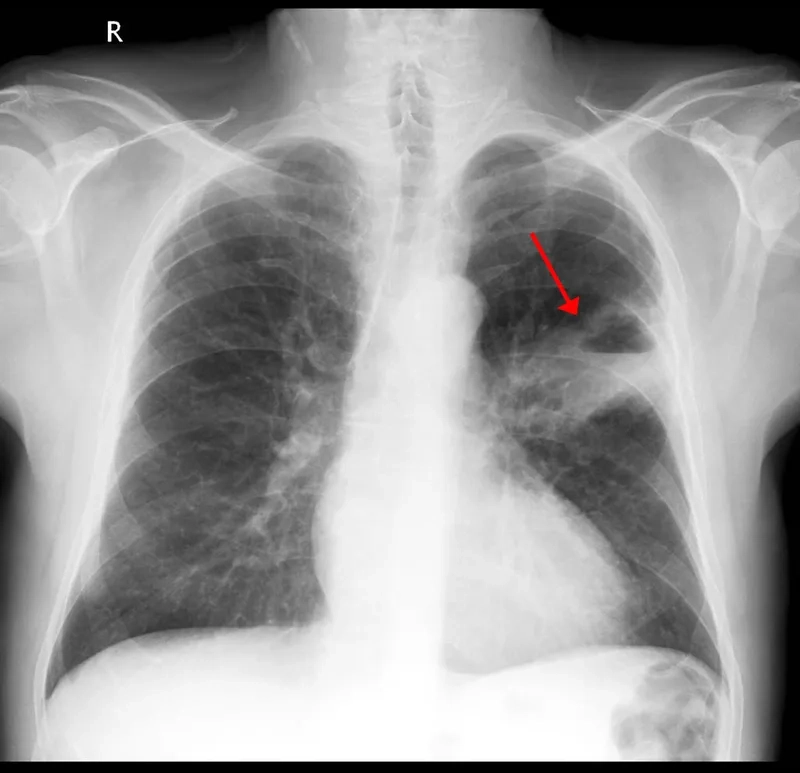

Image of the disease Lung Cancer - and other variables